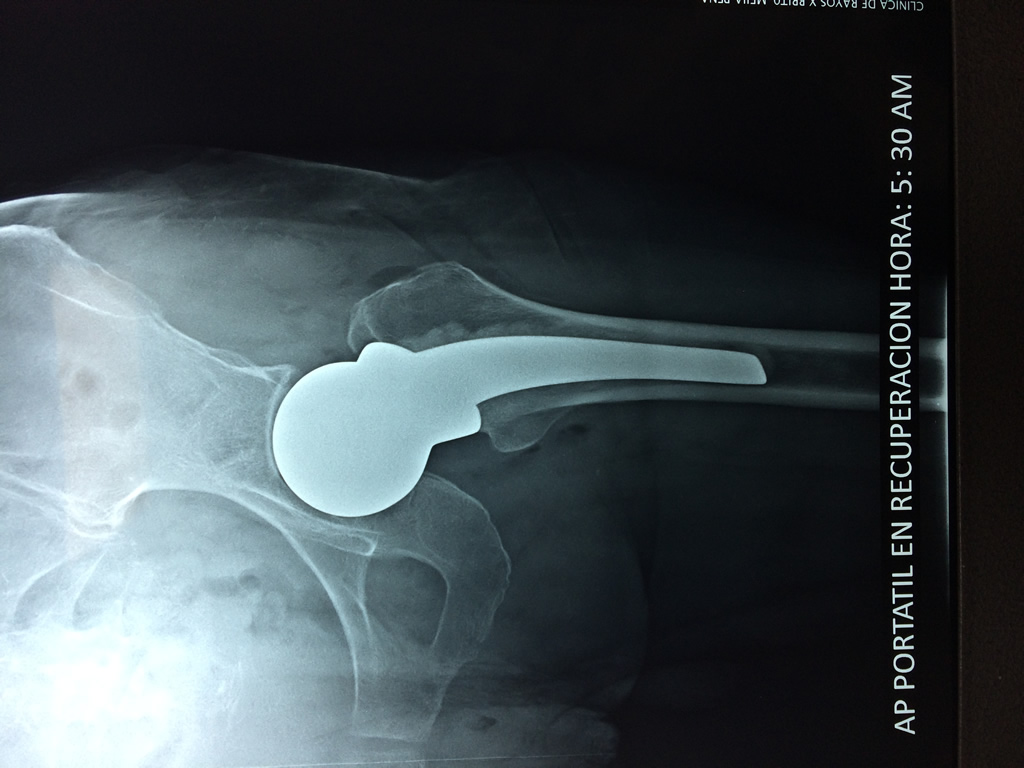

Cirugías de Codos - Cadera

La cirugía de fractura de cadera se realiza para reparar una ruptura en la parte superior del hueso del muslo. Este hueso se denomina fémur.

Es parte de la articulación coxofemoral. Si una fractura de cadera no recibe tratamiento, es posible que deba permanecer en una silla o en la cama.